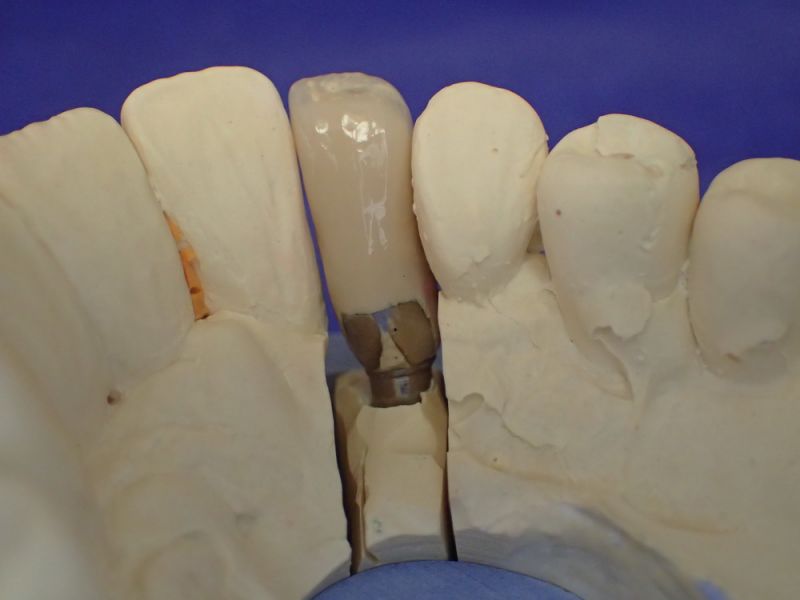

Kieler Patient erhält implantatgestützte Kronenversorgung 22

In diesem Fall wäre es sogar möglich gewesen auf das neue Implantat 22 zu verzichten und eine Versorgung auf den vorhandenen Implantaten zu begründen.

Das hätte aber zu einem wesentlich höheren wirtschaftlichen Aufwand geführt, weil die dann notwendige Prothetik, die von den Implantaten hätte entfernt und nachfolgend wieder neu hätte erstellt werden müssen, wesentlich teurer gekommen wäre, als ein neues Implantat mit einer neuen Krone darauf.